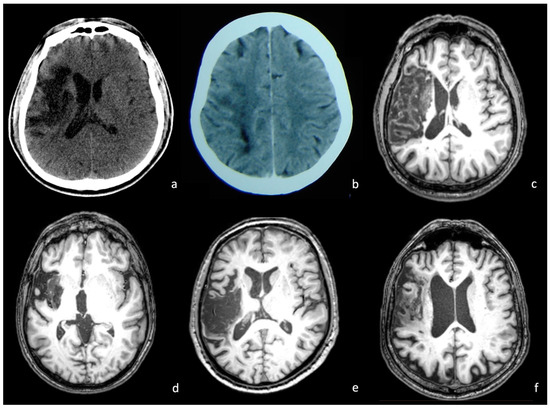

2.2. Neuroimaging Data